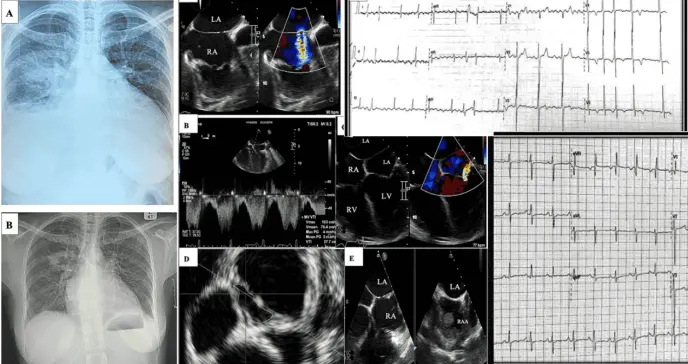

La radiografía de tórax inicial confirmó la presencia de congestión pulmonar, mostrando una silueta cardíaca agrandada, arterias pulmonares prominentes, derrame pleural derecho y consolidación en el lóbulo inferior derecho.

El electrocardiograma de 12 derivaciones mostró signos de agrandamiento de la aurícula izquierda, hipertrofia y distensión del ventrículo derecho, además de insuficiencia tricuspídea.

La ecocardiografía transtorácica (ETT) demostró un agrandamiento de la aurícula derecha e hipertrofia del ventrículo derecho, con un espesor de la pared libre de 7 mm. Se identificó una insuficiencia tricuspídea de moderada a grave, y la presión sistólica de la arteria pulmonar estaba significativamente elevada, estimada en 100 mmHg.

La fracción de eyección del ventrículo izquierdo estaba gravemente reducida al 20%. Una ecocardiografía transesofágica (ETE) más detallada reveló hallazgos críticos: una pequeña comunicación interauricular (CIA) con un área 3D de 0,42 cm² que provocaba un cortocircuito de izquierda a derecha, y una membrana en la aurícula izquierda, por encima de la válvula mitral, consistente con un cor triatriatum.

Esta membrana presentaba un defecto que medía 1,3 cm² en la reconstrucción 3D, con un gradiente medio transorificio de 3 mmHg, el cual probablemente fue subestimado debido al estado de bajo gasto cardíaco. Adicionalmente, se observó una insuficiencia mitral funcional excéntrica de moderada a grave y se detectó un gran trombo en la orejuela de la aurícula derecha.